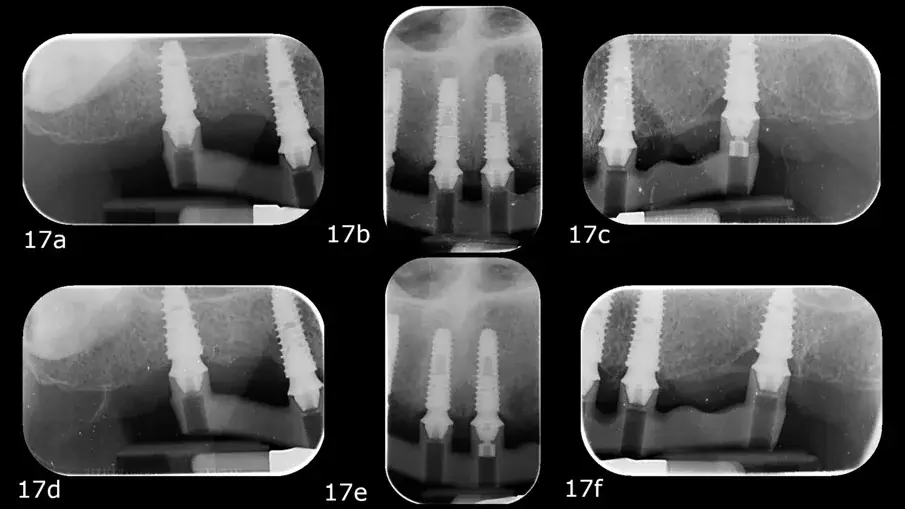

При второто посещение беше тестван PMMA прототип, поддържан от метална лента, за естетична и функционална точност. Пасивното прилягане на металната конструкция беше оценено с помощта на теста с един винт (Sheffield) и тактилна проверка с дентален експолорер (фиг. 15–17a–f).15, 16

Фиг. 17а–е: Периодични рентгенови снимки по време на теста с един винт.